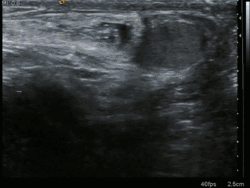

Een liesbreuk of hernia inguinalis[1] is een aandoening die bestaat uit een uitstulping van het buikvlies in de liesstreek, waardoor organen die normaal in de buikholte zitten (zoals de dunne darm) uit gaan puilen.

Een arts kan het bestaan van een liesbreuk eenvoudig vaststellen. Omdat de kwaal niet vanzelf herstelt kan een operatieve ingreep nodig zijn. Traditioneel wordt een liesbreuk verholpen door het buikvlies te herstellen met weefsel van de buikwand zelf. Vaak wordt daarvoor ook een kunststofmatje gebruikt, dit is de 'Lichtenstein-methode'. Sinds eind jaren 1990 kan een liesbreuk ook door middel van een kijkoperatie (laparoscopische procedure) worden behandeld.